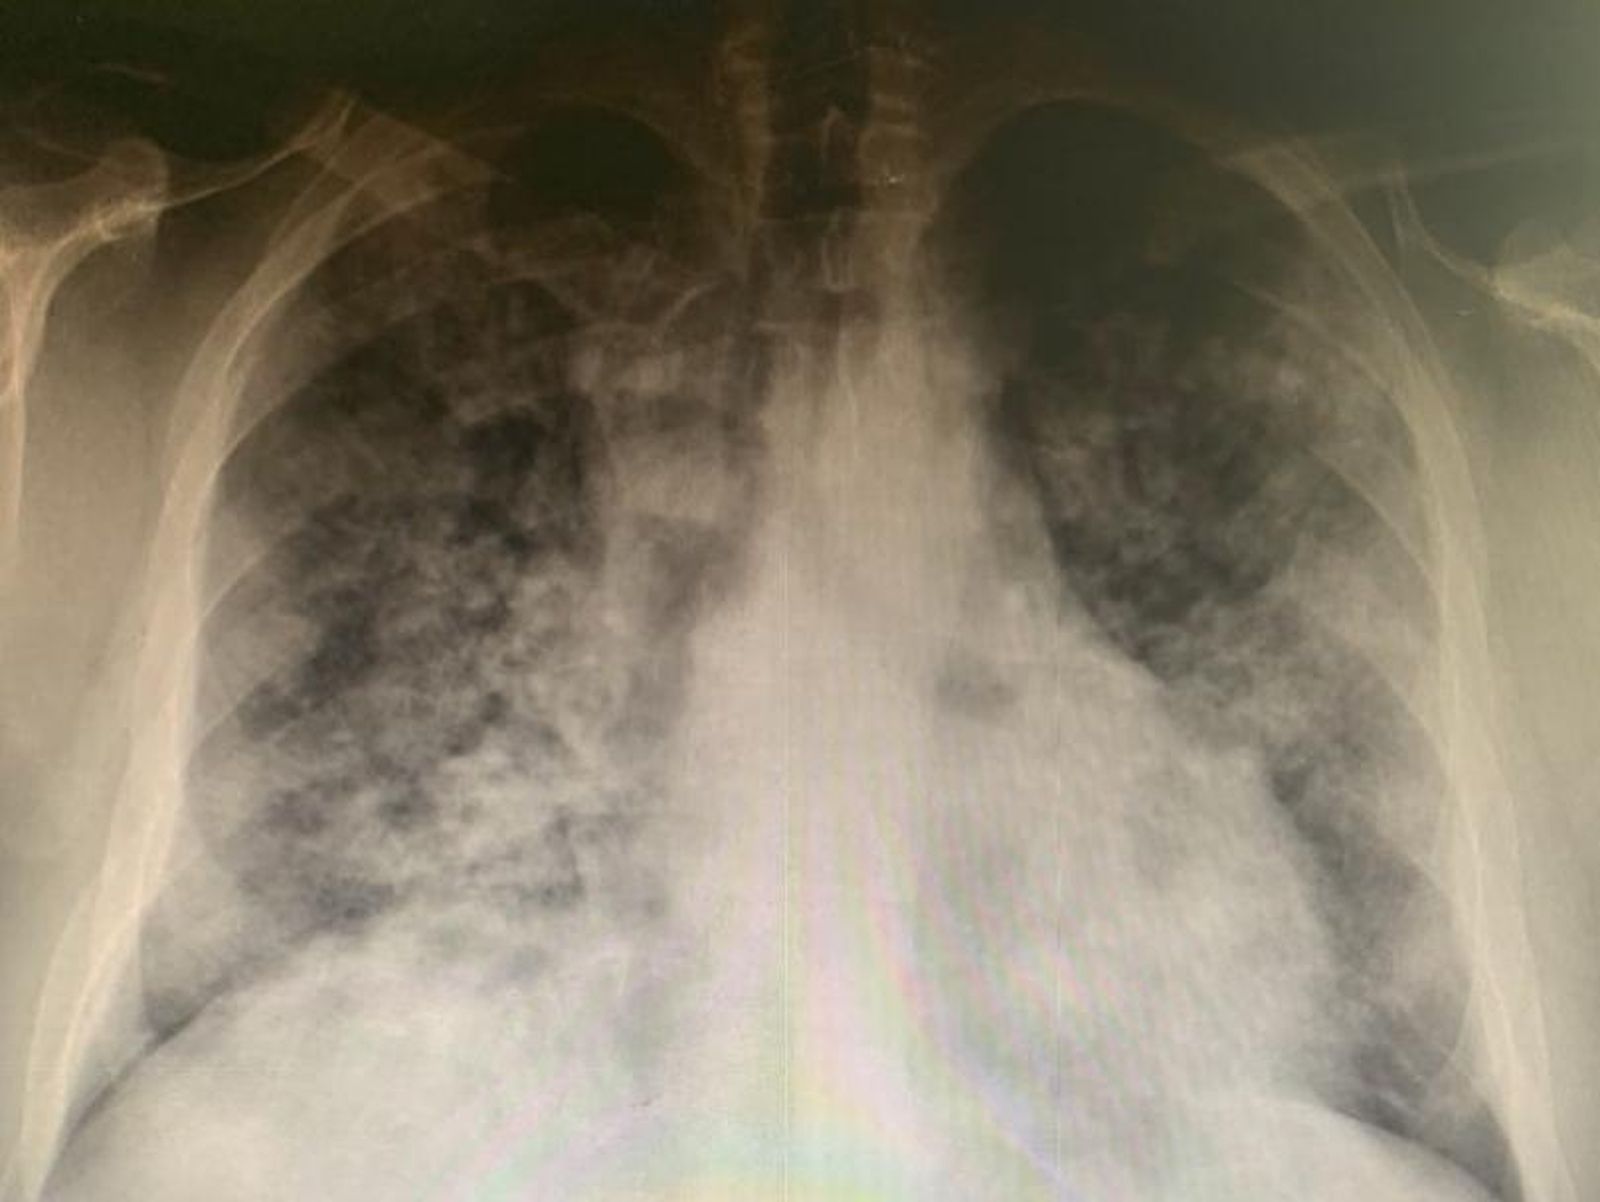

Con 44 años y sin otras enfermedades, explica el doctor, este paciente llevaba seis días sintiéndose mal, y los últimos cuatro los había pasado con fiebre. Tras dar resultado positivo en COVID-19 en un test de antígenos, la temperatura no bajaba pese a seguir el tratamiento que le habían puesto.

Acudió a Urgencias con un 67 por ciento de saturación y 40 respiraciones por minuto, según ha detallado el doctor García Criado que, después de estabilizarlo, le comunicó que iba a ser trasladado a la UCI.